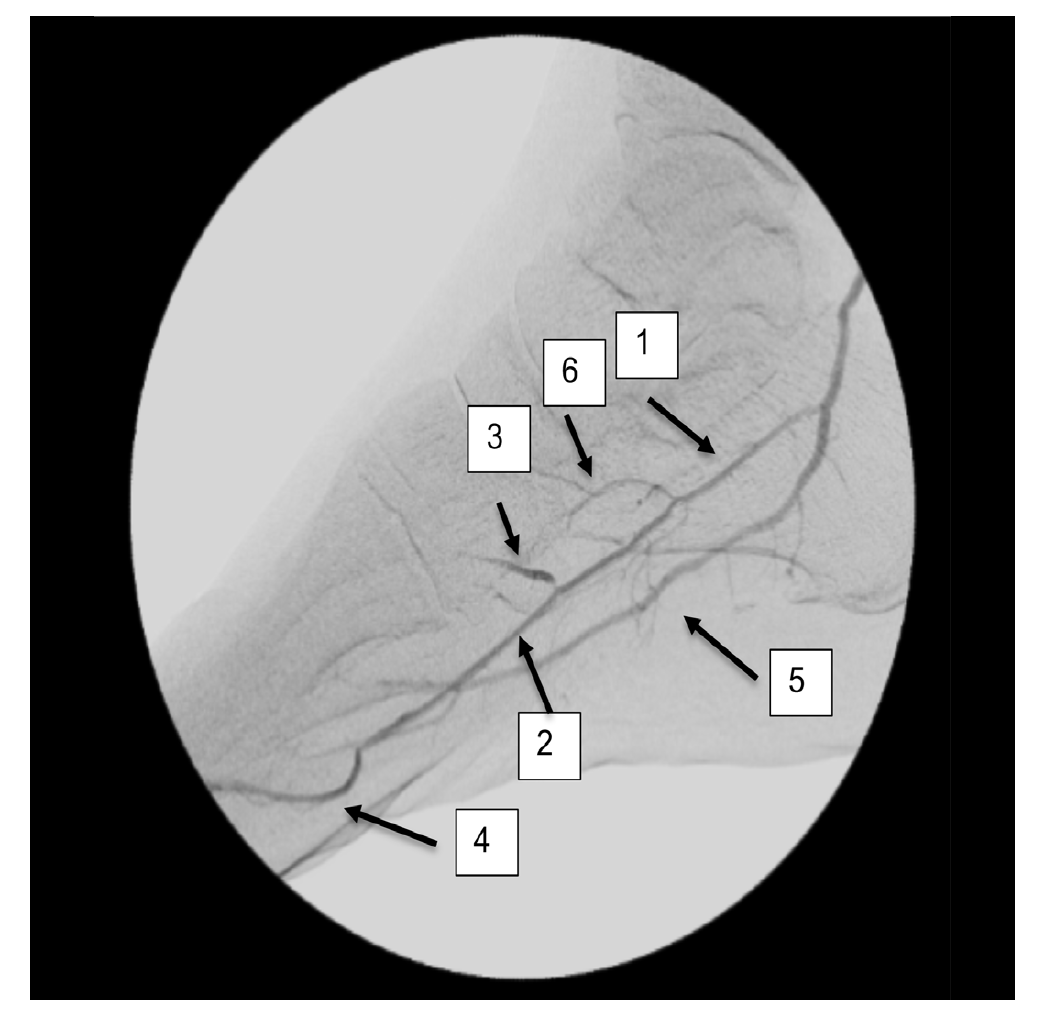

However, the entirety of the medial plantar artery (MPA) distribution was chronically occluded shortly after take-off (Figure 2E and Figure 2F). Super-selective angiography revealed chronic total occlusion of the medial branch of the first common plantar digital artery arising from the first plantar metatarsal artery (Figure 2G). Angiography also revealed an occluded accessory branch arising medially from the superficial branch of the MPA.

The anatomy of the arteries supplying the hallux is complex, with variants being common. In this patient, an atypical accessory branch arising from the superficial branch of the MPA was present. While the arterial anatomy of hallux-supplying arteries and its corresponding variants are not readily discussed in recent literature, certain textbooks do depict an accessory branch arising from the superficial branch of the MPA.2 The accessory branch of this patient, in particular, communicated with the first dorsal metatarsal artery arising from the DPA (Figure 2F) and the superficial branch of the MPA communicated with the medial branch of the first common plantar digital artery arising from the LPA (Figure 4C). In general, using the angiosome concept, the blood supply to the hallux consists of 3 main avenues: (1) the first dorsal metatarsal branch arising from the DPA; (2) the plantar digital arteries arising from the first plantar metatarsal artery, which is a branch of the LPA; and (3) the superficial branch of the MPA.3,4 The latter 2 sources of blood supply were absent in this case.